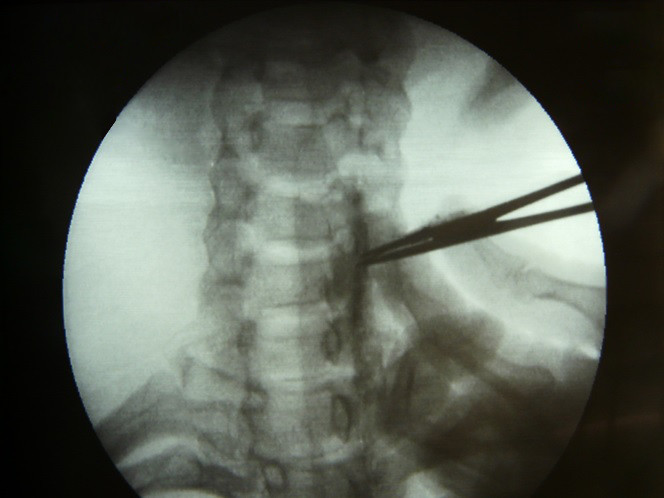

Fig.1. Localización del sitio de introducción de la aguja espinal a un lado del proceso unciforme del lado izquierdo de C-6.

2/6

Fig.3. Infiltración piel a nivel de C-6 para introducción de aguja espinal.

4/6